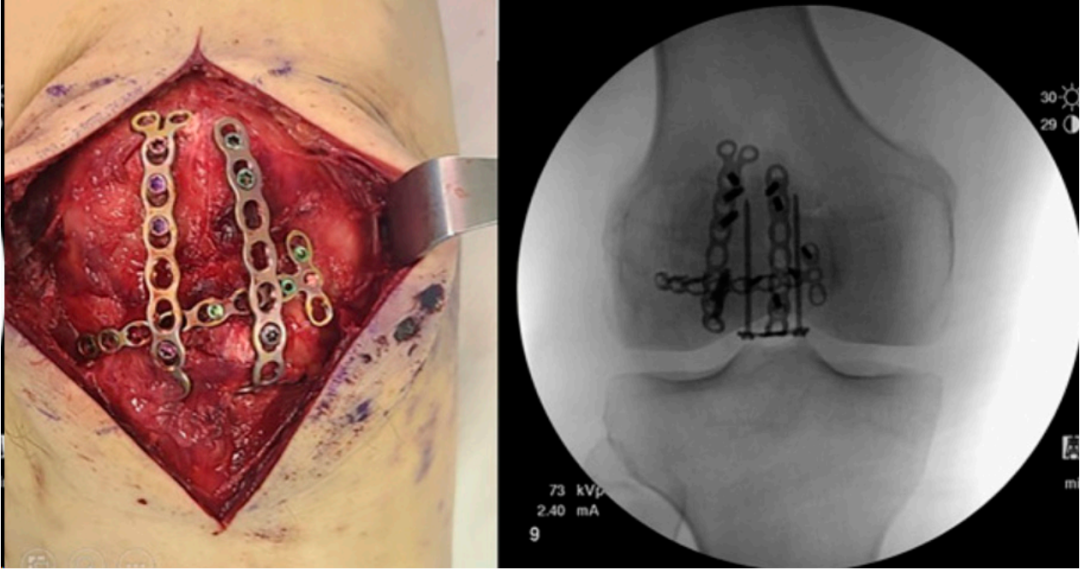

Yoo等人概述了一种使用锁定加压微型钢板结合长锁定螺钉/空心螺钉处理多块粉碎性髌骨骨折的手术技术(图4)。该研究纳入了20例AO/OTA 34-C3骨折患者,他们接受了基于2.4 mm LCP Compact Hand微型钢板(DePuy-Synthes:registered:, Warsaw, IN, USA)的内固定治疗,平均随访15个月。这些常用于手部骨折的低切迹植入物与其他固定方法一起使用,例如空心螺钉(九例)、环扎(两例)和钢丝固定(五例)。

微型钢板和锁定螺钉不仅提供了角度稳定性,还降低了螺钉拔出的风险。根据骨折形态,每个病例使用的钢板数量为2至5块(平均2.8块微型钢板)。平均骨愈合时间为15.6周(范围10至40),未报告固定失效或术后并发症病例,包括有症状的内植物。所有患者在最终随访时平均活动范围(ROM)达到130度,平均Lysholm评分为90.4。该研究表明,使用Compact Hand微型钢板进行髌骨骨折接骨术可以提供足够的机械稳定性以实现早期ROM,且无术后并发症。

图4. 描绘了使用锁定加压微型钢板固定粉碎性髌骨骨折,并展示了影像学图像。

图5. 展示了一种低切迹髌骨钢板。